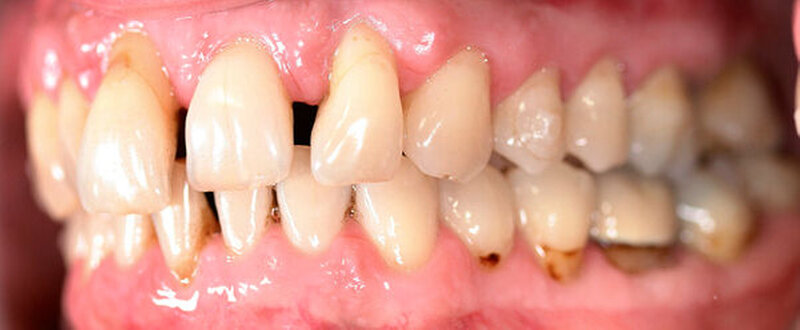

Anamnestisch lagen keine Besonderheiten vor. Es ist jedoch zu vermerken, dass ein regelmäßiger Alkohol-, Koffein- und Nikotinkonsum zugrunde lag. Intraoral zeigte sich ein bereits konservierend versorgtes permanentes Gebiss mit aktivem und inaktivem kariösen Geschehen. Große Anteile der Zahnhälse lagen nach Zahnfleischrückgang in Kombination mit Knocheneinbrüchen frei. Zahn 27 wurde bereits extrahiert.

Eine Beurteilung der parodontalen Situation an Zahn 11 offenbarte mesial und distal Sondierungstiefen von jeweils 6 mm.

Kieferorthopädisch imponierte beidseits eine neutrale Verzahnung bei einem tiefen Biss von 5 mm – bedingt durch die Verlängerung beider Frontzahngruppen. Besonders Zahn 11 zeigte eine erhebliche Verlängerung und Protrusion mit einer sagittalen Frontzahnstufe von 5 mm. Sowohl die Frontzähne im Ober- als auch im Unterkiefer wiesen eine lückige Beziehung zueinander auf (Abbildung 1).

Röntgenologisch stellte sich im Orthopantomogramm der bereits intraoral ersichtliche horizontale und vertikale Knochenabbau mit Attachmentverlust an einzelnen Zähnen dar. Die Erhaltungswürdigkeit einzelner Zähne war aufgrund des starken Knochenverlustes beziehungsweise der Beeinträchtigung des Halteapparates als kritisch zu beurteilen.

Zudem wurde die Diagnose einer Parodontitis gestellt, die eine Rücküberweisung an den Hauszahnarzt erforderlich machte (Abbildung 2).